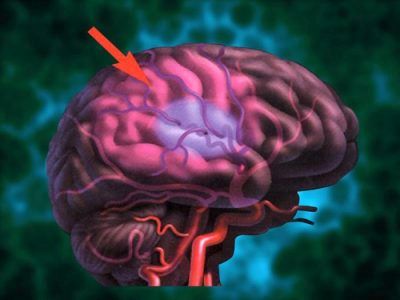

Нетравматичне внутрішньомозковий крововилив

Необхідно відзначити, що при різкому підвищенні тиску стінки артерій стають проникними і починають пропускати в речовина мозку не тільки протеїни, плазму, а й еритроцити. Проникнувши в мозкову речовину, кров починає його руйнувати, а сусідні з гематомою нервові клітини випробовують здавлювання. Це супроводжується різким підвищенням внутрішньочерепного тиску.

Крім крововиливу в саме речовина мозку, є ще одна форма геморагічного інсульту - подоболочечное або субарахноїдальний крововилив, т. Е. Крововилив в павутинну оболонку мозку. Таке захворювання розвивається в основному при розриві аневризми (виріст судинної стінки) на тлі різкого підвищення тиску і супроводжується такими ознаками: